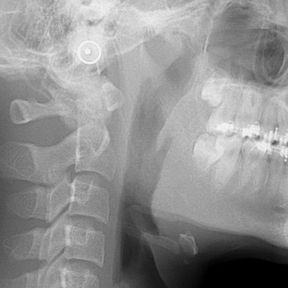

얼굴 골격의 성장에 문제가 있는지를 파악하기 위한 적절한 시기는 초등학교 입학 전인 6-7세경입니다. 이때는 유치에서 영구치로 교환되는 시기로서 부정교합 여부가 결정되는 중요한 시기이므로 이 시기를 잘 관찰하여 부정교합을 예방하는 것 또한 중요합니다. 교정의 정확한 시기는 6개월 간격으로 치과에 정기적으로 내원하여 성장 분석을 받은 후 결정하는 것이 좋습니다.